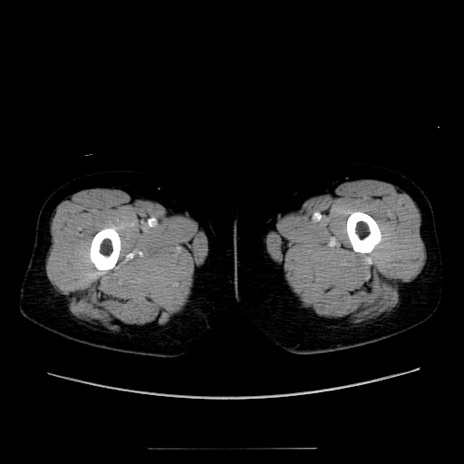

症例5(横断像)

【症例】70歳代女性

【主訴】お腹が張る

【現病歴】1週間くらい前から腹部膨満の自覚あり。昨日夜から増悪したため、本日救急外来受診。

【身体所見】意識清明、BT 36.5℃、BP 165/106mmHg、HR 80bpm、SpO2 98%、腹部:膨満、軟、自発痛・圧痛なし、触診にて不快感あり、腸蠕動音:減弱

【データ】WBC 12600、CRP 1.04